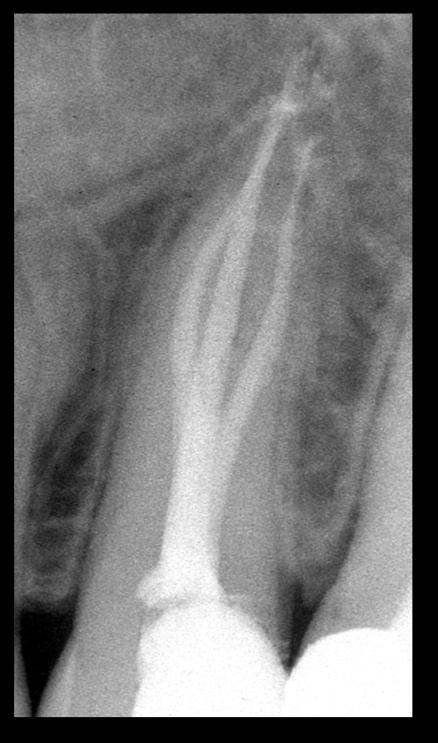

Apertura della corona fino ad arrivare alla camera pulpare (tale trattamento viene eseguito tramite anestesia locale). Si rimuove la polpa e si cercano i canali radicolari del dente, una volta trovati si estirpano i nervi. Si allargano e si puliscono i canali del dente, (tramite strumenti al Nichel titanio o strumenti manuali) prendendo anticipatamente le misure dei canali (per non uscire oltre apice). Si disinfettano i canali e si eseguono vari lavaggi tra un passaggio e un altro per elimininare il fango dentinale. Il medico a questo punto verifica la possibilità di chiudere definivamente i canali o lasciare il dente in prova, inserirendo nei canali un disinfettante e eseguendo una chiusura provvisoria. Al momento di chiudere il dente definivamente, questo viene preparato rieseguendo le misure dei canali da chiudere ed usando per la stessa lunghezza del canale, un cono di guttaperga del diametro necessario. Si scalda il cono in guttaperga e si inserisce nel canale. Durante il trattamento endodondico vengono effettuati una serie di esami radiografici per verificare i risultati, le lunghezze, la forma dei canali.

L'esame radiografico, fondamentale per porre diagnosi in odontoiatria, in endodonzia è irrinunciabile perché è l'unico strumento che ci permette di "vedere" all'interno della radice del dente, è quindi molto importante la possibilità di effettuare lastre con apparecchiature digitali che emettono un quarto della dose di raggi emessa da un radiografico tradizionale e che permettono di conservare la radiografia endorale in una cartella informatica del paziente senza possibili alterazioni nel tempo.